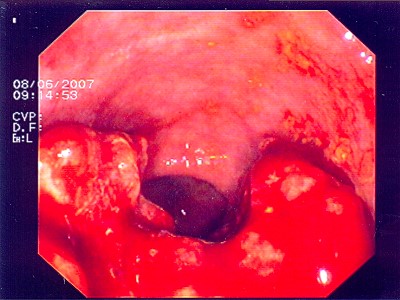

Abb. 3: Hier liegt das bösartige Gebilde exakt im Bereich des Überganges von Dick- zu Dünndarm. Die Umrisse des Überganges (bauhin'sche Klappe) kann man noch erkennen. Abb. 3: Hier liegt das bösartige Gebilde exakt im Bereich des Überganges von Dick- zu Dünndarm. Die Umrisse des Überganges (bauhin'sche Klappe) kann man noch erkennen.